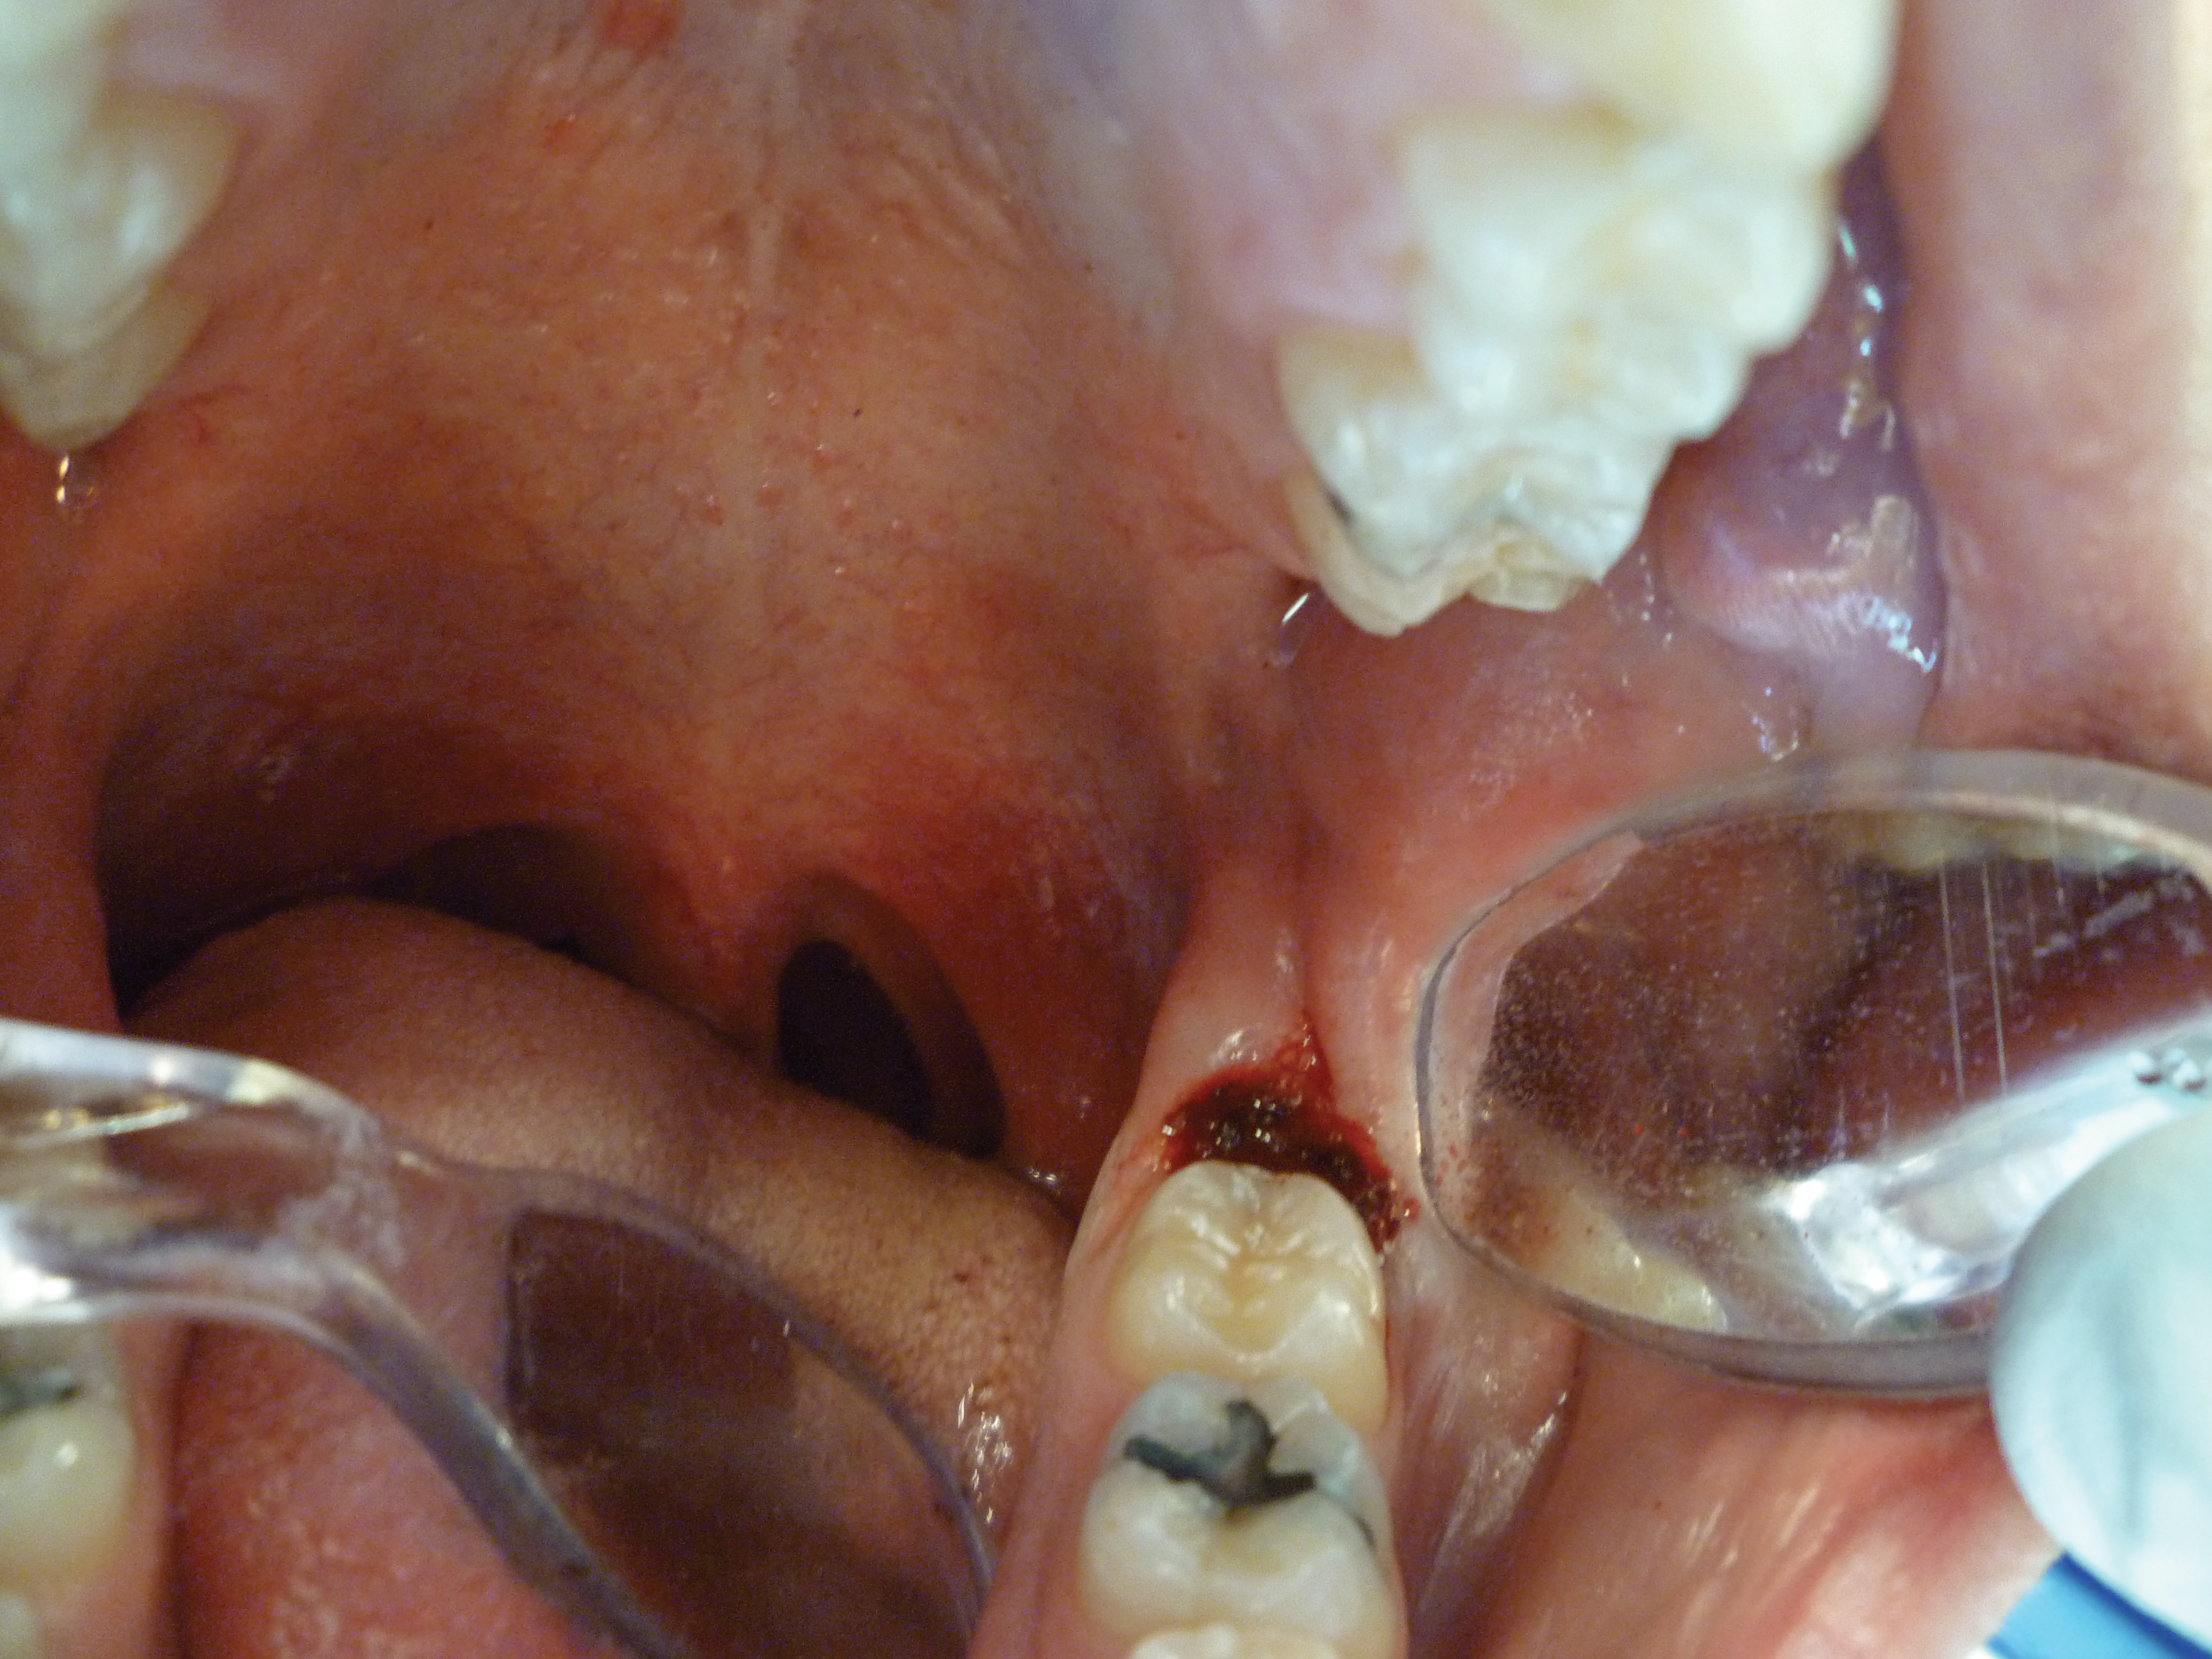

The patient presented with a raised, inflamed, painful operculum distal to the left mandibular second molar (Figure 3). The lesion was red, edematous, and bled easily. A periodontal pocket on the distal of the second molar was >6 mm deep. There was no evidence of abscess.

Fig 3. Preoperative view of the inflamed operculum.

Figure 3